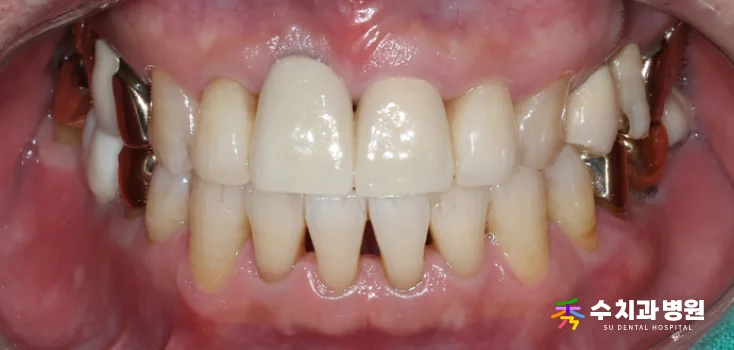

[치료 전 사진] (촬영일: 2025년 06월)

환자분은 앞니 하나가

점점 아래로 처지는 느낌이 들어

걱정스러운 마음에 내원하셨습니다.

정밀 검사 결과, 오른쪽 대문니(앞니)는

과거에 신경치료를 받았던 이력이 있었습니다.

뿌리 쪽 잇몸뼈 흡수가 심하게 진행되어

치아가 제 위치를 잡지 못하고 있었습니다.

치아가 심하게 흔들리는 상태였기 때문에

안타깝게도 발치가 불가피했습니다.

또한 옆 치아의 색상도 변색이 진행되어

심미적인 개선이 시급했습니다.